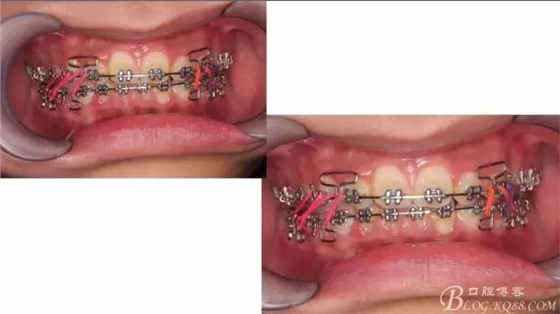

接下來盡管配合些雙側后牙對角牽引,咬合關系依,不盡人意。

下頜配合多曲方絲,三角牽引,調整咬合。

中線不齊,咋辦?繼續(xù)哄哄患者配合,2牽+斜牽。

努力沒有白費,中線基本對齊!